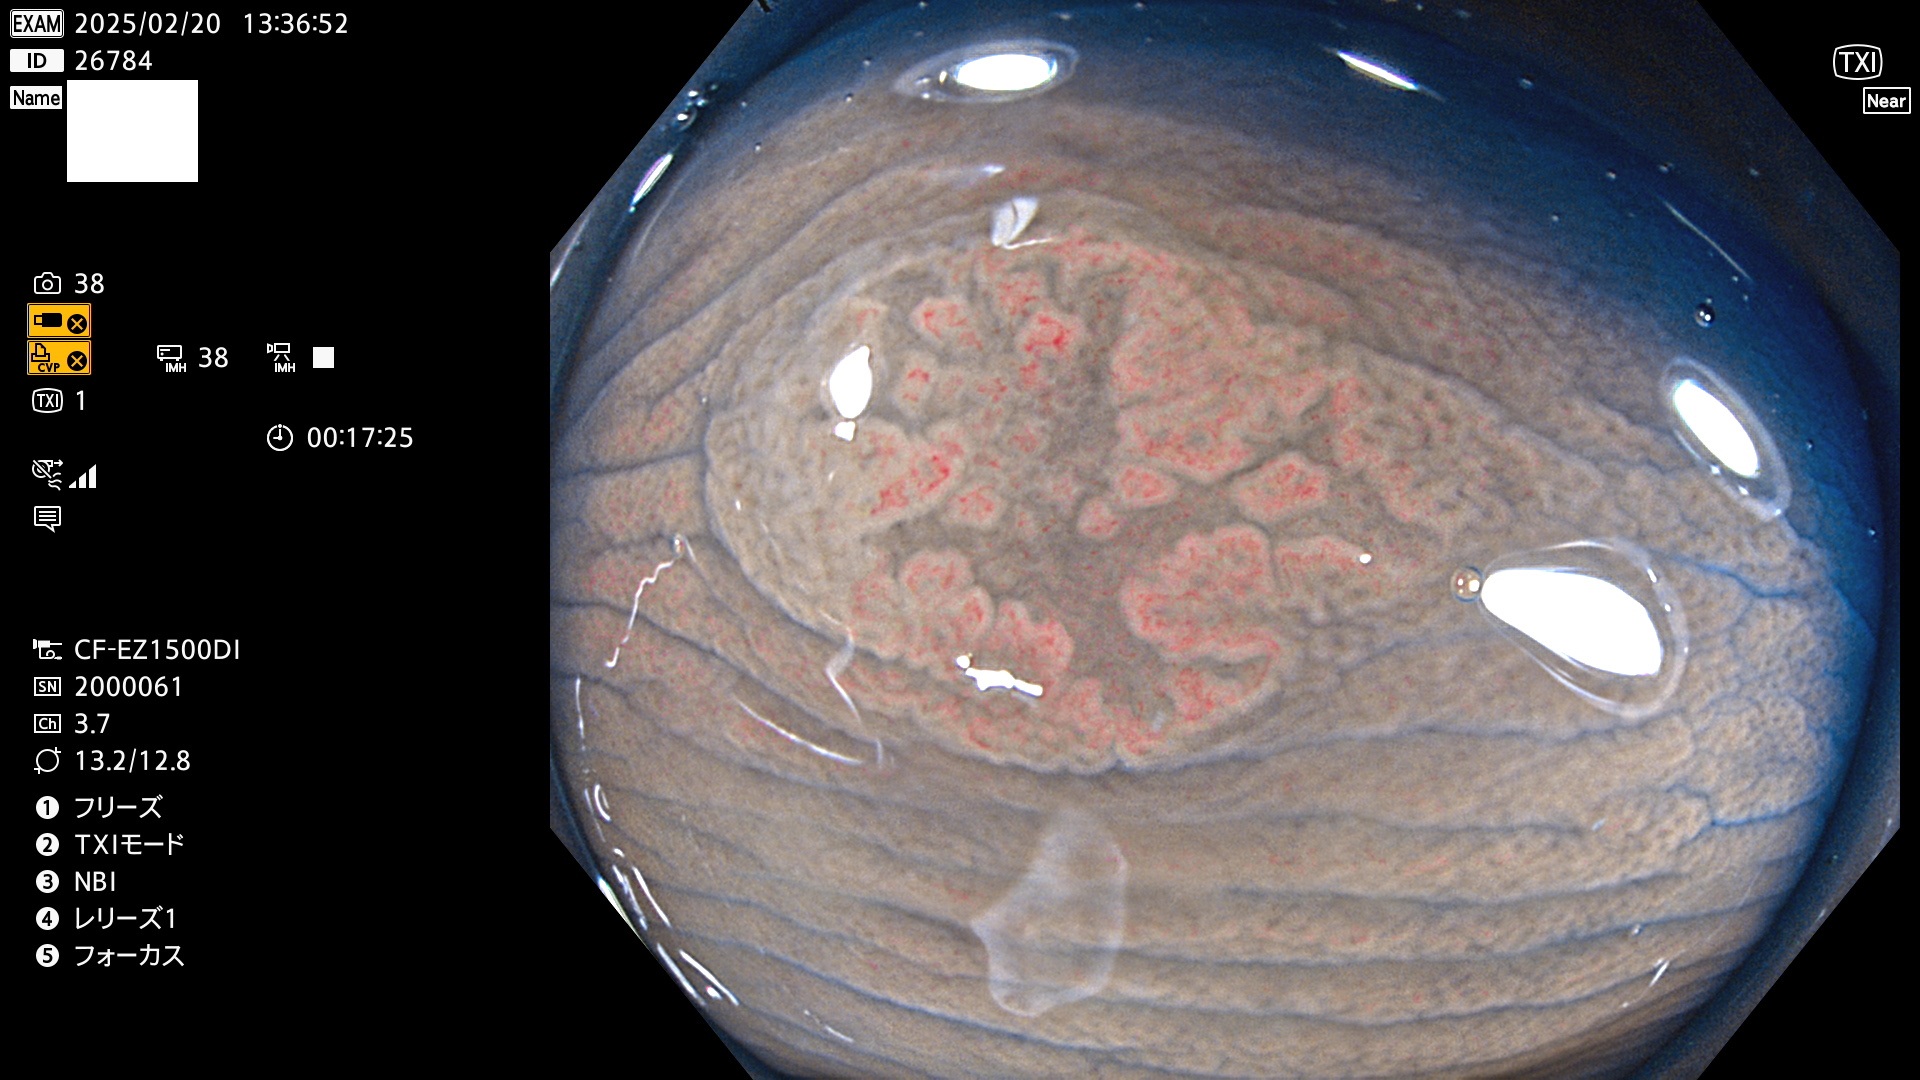

完全に平坦な物をUb、陥凹している物をUcと呼びます。最も発見が難しく危険な病変です。

毎週の検査(木・金・土・日)に発見されたUb、Uc型・腺腫を、その週の日曜の夜にUPし1週間、提示します。

抽出の対象期間 2025年2月20日〜2月23日の4日間(48件の検査)8個 (8/48=16%)